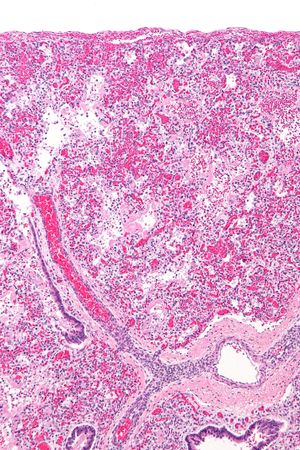

임상적으로 ARDS는 폐렴, 호산구성 폐렴, 특발성 폐렴, 급성 섬유성 폐렴 등 다양한 병리학적 소견과 연관될 수 있으며, 그중 가장 흔한 것은 미만성 폐포 손상(diffuse alveolar damage, DAD)이다. DAD는 폐 조직의 광범위한 염증을 특징으로 한다. 폐 손상을 유발하는 초기 자극은 일반적으로 국소 상피세포와 내피세포에서 사이토카인 및 기타 염증 매개체의 분비를 촉발한다.

이후 호중구와 일부 T-림프구가 염증이 발생한 폐 조직으로 빠르게 이동하여 염증 반응을 증폭시킨다. 조직학적으로는 미만성 폐포 손상과 함께 폐포벽에 유리질 막(hyaline membrane)이 형성되는 것이 특징이다. 이러한 병태생리의 정확한 유발 기전은 아직 완전히 밝혀지지 않았지만, 염증 반응과 기계적 스트레스의 역할에 대한 연구가 진행 중이다.